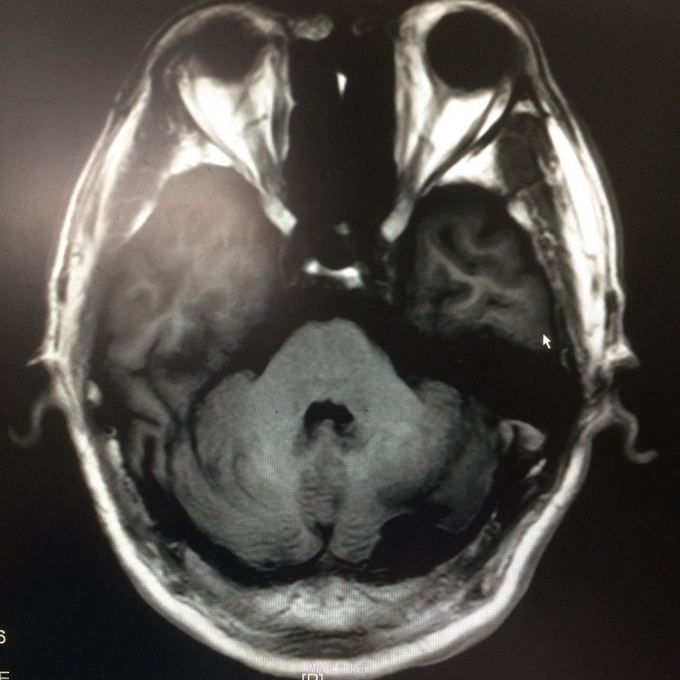

主诉:头晕头痛2年 病史:2年前无明显诱因出现头痛,呈刺痛,程度较重,伴头晕、天旋地转感,1年前查头颅MR提示:左侧小脑半数囊性病变,考虑血管母细胞瘤

查体:神志清楚,病理证阴性 辅助检查:头颅MR提示左侧小脑半数后部囊状占位灶,考虑良性病变。

诊断:左侧小脑血管母细胞瘤 处理:行左侧小脑占位病变切除术,术后病理提示:符合血管母细胞瘤。